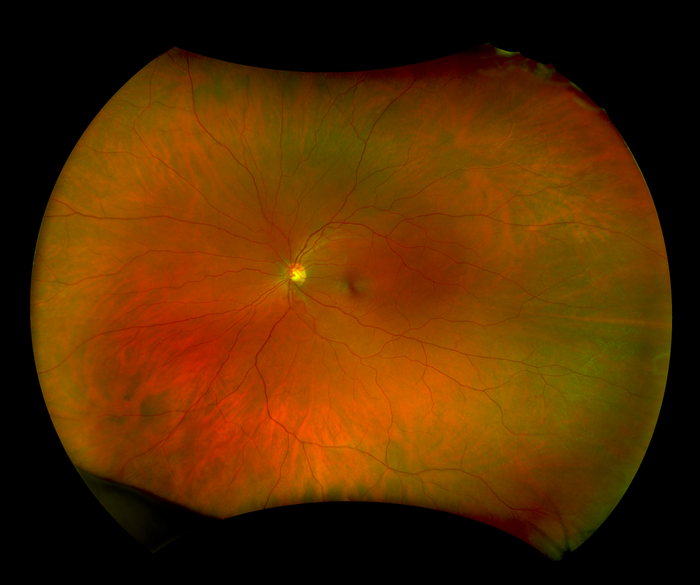

With California, Optos has incorporated new technology enabling practitioners to see more, discover more, and effectively treat more ocular pathology thus promoting patient health. In addition to a field of view of 200° or 82% of retina in a single shot, California, offers the following benefits:

- Visibility of 50% more of the retina when compared to other conventional imaging devices

- 4-in-1 Color Depth Imaging™ produces optomap colour rgb, optomap colour rg, optomap Sensory Retina and optomap Choroidal in a single shot.